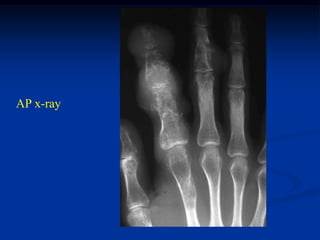

Case #562

31 year female with enchondroma great toe

Amputation

specimen

Photomic